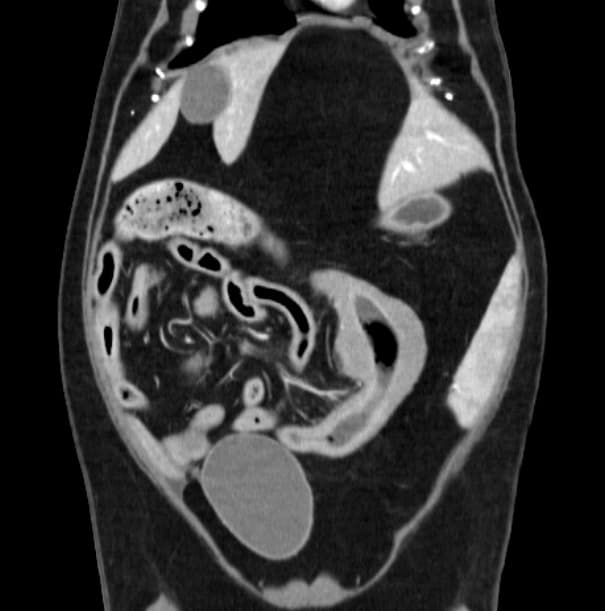

간, 담도 수술은 수술뿐만 아니라, 수술 후 중환자 관리도 중요하기 때문에 외과와 내과의 협진이 매우 중요합니다. 동탄시티동물의료센터에서는 최신 수술 장비의 도입으로 간담도 수술에서 출혈 및 부작용을 최소화 하였으며, 수술 후 협진 시스템을 통해 수술 후 관리에도 최선을 다하고 있습니다.

간종양

최고 사양 영상 장비를 활용한 정밀한 전이 평가

외과 협진 시스템을 통한 신속한 종양 수술

동탄 1 신도시 최초 Aquilion CX/128 slice CT를 동물병원에 도입하였습니다. 최고 사양 CT 모델 Aquilion CX/128 slice를 활용하여 0.5 mm의 얇은 128개의 단면 영상을 신속히 획득 할 수 있어 마취 시간을 단축시킬 수 있습니다. 또한, 128 슬라이스의 고화질의 CT 영상을 통해 영상 왜곡을 최소화하고 X-ray에서는 확인하기 힘든 5 mm 이하의 미세 병변도 확인이 가능하여 정확한 진단을 할 수 있습니다. 심화 진단이 필요한 경우, 조영제 인젝터를 통한 동맥기 촬영으로 종양 유래 확인, 간 질환 진단, 심혈관계 진단이 용이합니다. 저희 동탄시티동물의료센터에서는 본원 환자뿐 아니라 1차 동물 병원과의 CT 촬영 의뢰 시스템을 통해서 원활한 협진이 가능하도록 최선을 다하고 있습니다.

0164 채널 CT 촬영을 통해서 신속하게 고화질 영상을 얻어, 종양 유래 확인 및 전이 평가, 간문맥단락증(PSS), 선천적 뼈 기형과 같은 심화된 진단을 할 수 있습니다.